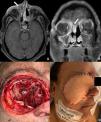

Resection of malignant tumors located in the anterior and middle fossae of the skull base requires thorough anatomical knowledge, as well as experience regarding the possible reconstructive options to resolve the resulting defects. The anatomical and functional relevance of the region, the complexity of the defects requiring reconstruction and the potential complications that can occur, represent a true challenge for the surgical team. The goal of this study is to describe the microsurgical reconstructive techniques available, their usefulness and postoperative complications, in patients with malignant tumors involving the skull base.

ResultsTwenty-four patients required reconstruction with FF; 14 were male (58.3%) and mean age was 54.9 years. Sarcoma was the most frequent tumor histology. Free flaps used were the following: anterolateral thigh, rectus abdominis, radial, latissimus dorsi, iliac crest and fibular. Complications occurred in 6 cases and no deaths were reported in the study group.

ConclusionFree flaps are considered one of the preferable choices of treatment for large skull base defects. In spite of the complexity of the technique and the learning curve required, free flaps have shown to be safe, with a low rate of serious complications. For these patients, the surgical resolution should be performed by a multidisciplinary team.